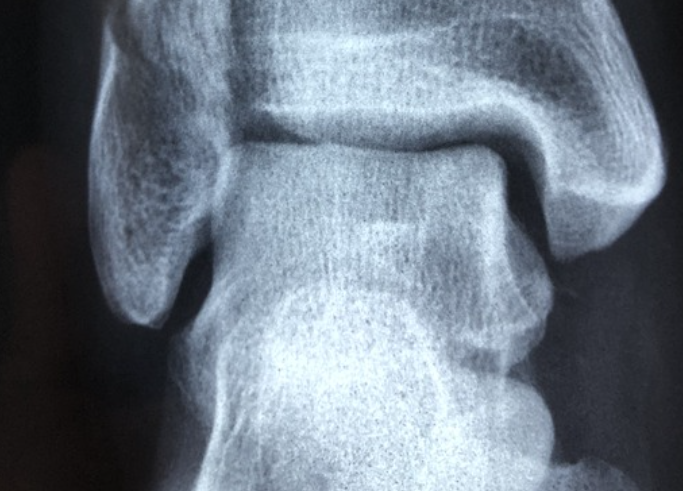

뼈가 가지는 특성으로 인해 질환 초기에는 특별한 증상이 나타나지 않습니다. 초기 증상으로는 척추뼈가 약해져 휘거나 압착되어 키가 줄어들 수 있습니다.

골절의 위험도 증가합니다. 심한 경우 물건을 들려고 허리를 구부리거나 기침을 하는 와중에도 쉽게 뼈가 부러지기도 합니다.

골다공증은 남성에 비해 여성이 약 15배가 많이 발생하며 50대 이상에서 증가하는 질환입니다. 50~70대 여성은 주로 손목 골절이 나타나고 70대 이상의 경우 고관절이나 척추의 골절이 흔하게 발생됩니다.